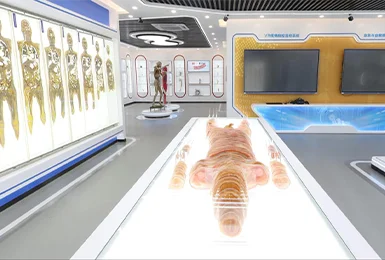

Zhengzhou Meiwo Science & Technology Co., Ltd established in 2009, is a comprehensive technology enterprise for medical education integrating R&D, production and sales. Meiwo Science has independent specimen production workshops and model production workshops covering an area of 10,000 square meters. Meiwo main products involve plastinated animal specimens, soft silicone anatomy models, high simulation soft anatomy models, human & animal anatomy softwares, 3D digital human specimen, biological microscope slides, animal skeletons, etc.

We are confident with our products which will enhance the medical anatomy lessons, teaching, curriculum, scientific research and exhibition show. Welcome!